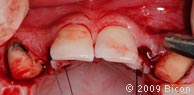

5. Ретракционные швы, удерживающие два небных лоскута.